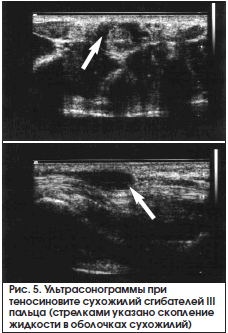

При ультразвуковом исследовании можно обнаружить изменение синовиальных оболочек и жидкостный компонент (рис. 5).

Аналогичные изменения выявляются при МРТ Т1- и Т2-взвешенном изображении (рис. 6).